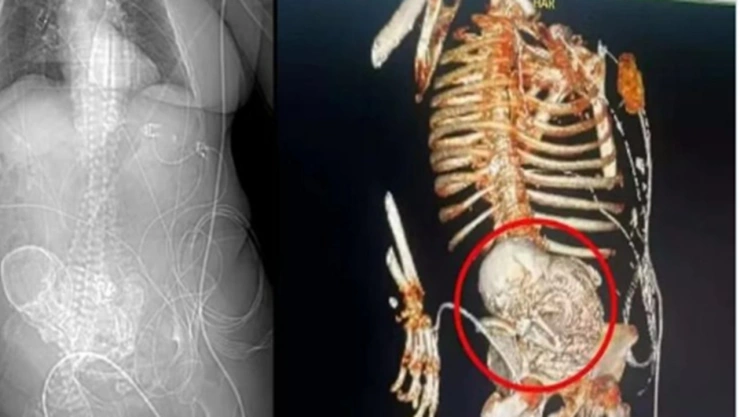

Una mujer de 81 años murió durante una cirugía luego de que le descubrieran un “bebé de piedra” o feto calcificado que llevaba en su interior desde hace más de 30 años. Los hechos ocurrieron en un hospital de Mato Grosso do Sul en Brasil.

De acuerdo con lo informado por el Hospital Regional Dr. José de Simone Netto en la ciudad de Ponta Porã, los hechos ocurrieron el pasado 14 de marzo de 2024, cuando la octogenaria acudió con una infección grave. Tras realizarle una tomografía, el equipo médico le encontró un "feto calcificado".

El hospital detalló que el llamado bebé de piedra que tenía la adulta mayor en su interior es una condición rara denominada 'litopedia', que es causada por un óvulo que se fertiliza fuera del útero y deriva en la muerte del feto y su posterior calcificación.

Asimismo detallaron que el equipo médico de urgencias decidió realizar la extracción quirúrgica del feto con el objetivo de "controlar la grave infección que sufría la mujer y que amenazaba su vida".La operación se llevó a cabo el 15 de marzo, pero la mujer terminó falleciendo al día siguiente.

Cabe señalar que la mujer habría cargado con este feto desde la última vez que tuvo un embarazo, entre hace 30 y 40 años atrás.